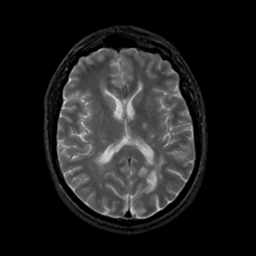

MR Study #12, May 12, 1991 -- Slice #28